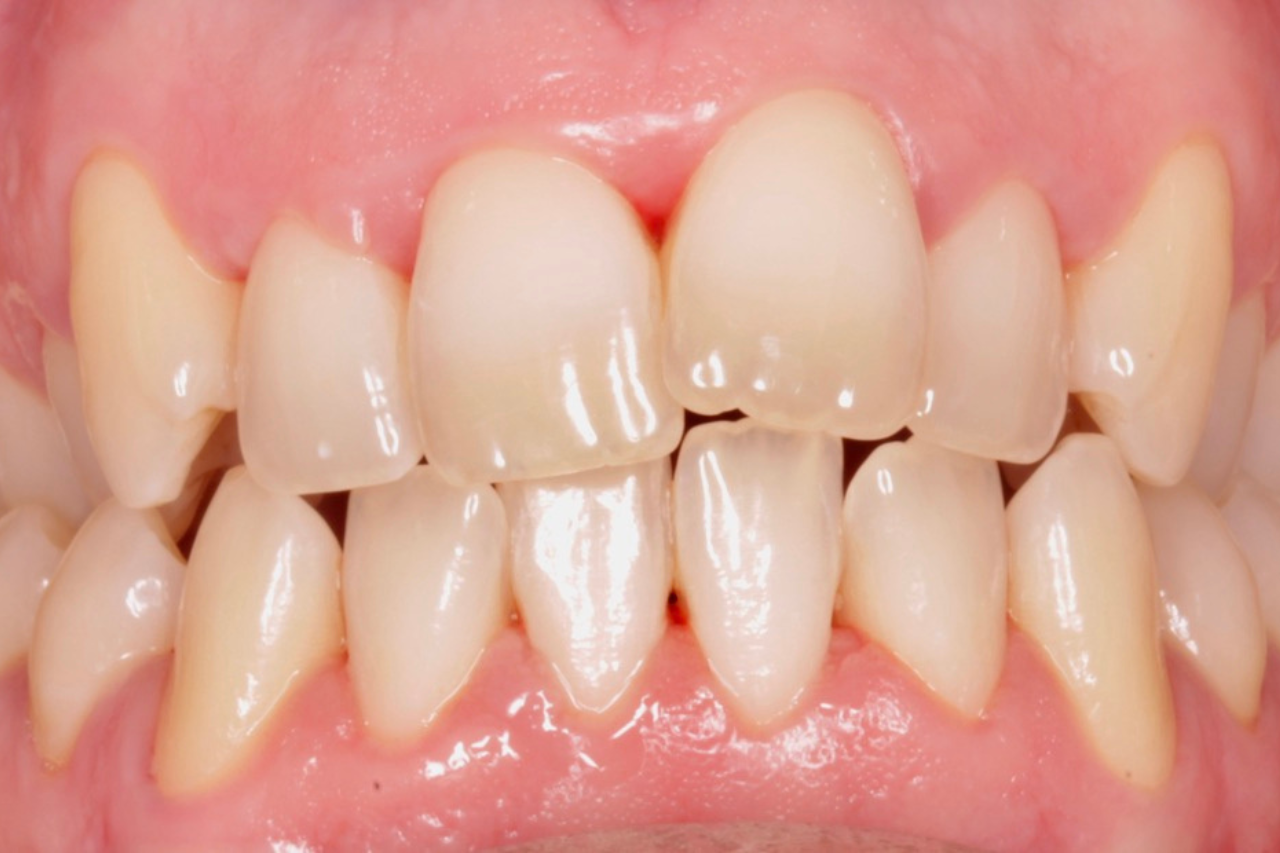

Este paciente acudió a Clínica Dental Urumea para mejorar la estética de su sonrisa. Primero se realizó un tratamiento de ortodoncia con alineadores transparentes Invisalign, para alinear y corregir la mordida cruzada.

Posteriormente, se realizaron blanqueamientos ambulatorios para mejorar

En este caso se ha optado por alineadores Vivera como método de retención.